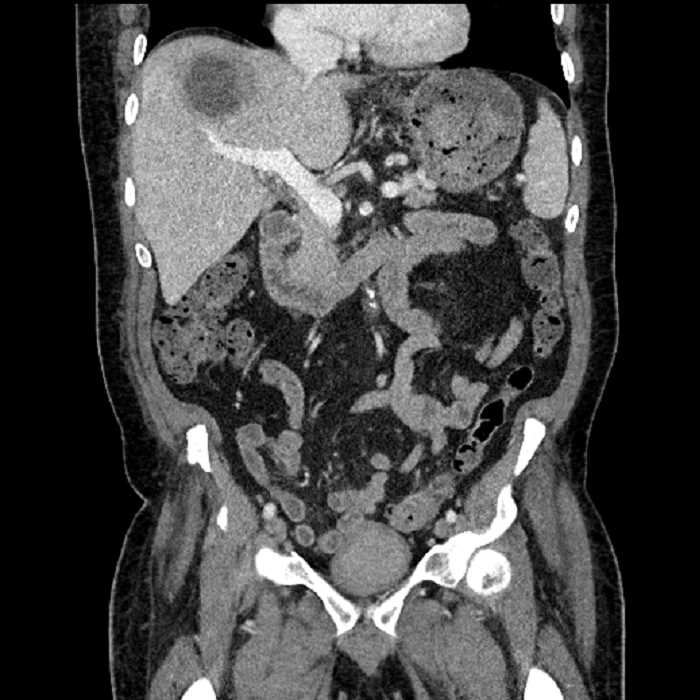

• Large fluid density structure in hepatic segments 7 and 8 measuring 10 x 7 x 7 cm with internal septation and circumferential ill-defined low density compatible with edema

• Peripherally enhancing subcapsular collections along the anterior margin of the left hepatic lobe measuring 3 x 1 cm and 2 x 1 cm

• Clearly marginated fluid density structure in segment 7 and several other scattered tiny hypodensities, which likely represent cysts

• Hepatic abscess

Acute sigmoid diverticulitis complicated by a small contained perforation and a large abscess in the right hepatic lobe. Additional small subcapsular abscesses along the anterior margin of the left hepatic lobe.

• The classic CT imaging appearance is a double target sign with internal low density surrounded by an internal enhancing rim (capsule) and a low density external rim (edema)

• Abscesses may be unilocular or multilocular

• Gas is present in a minority of cases

Hepatic abscess showing the double target sign with low density internally surrounded by a thin inner enhancing rim (red arrow) and ill-defined outer low density rim (yellow arrow). Blue arrow indicates an internal septation. Red arrows: additional smaller subcapsular abscesses. Red arrow: focal contained perforation associated with diverticulitis.